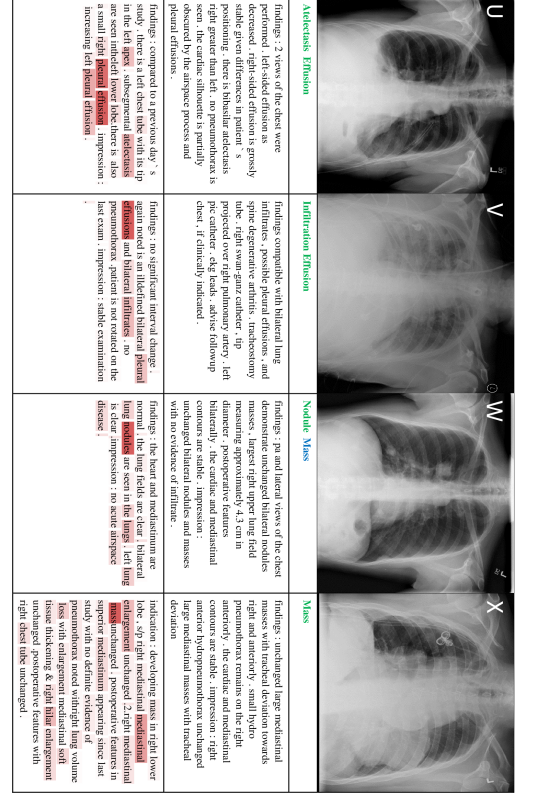

In this section, we present 20 more classification and reporting results (case E-X) from the proposed TieNet in addition to the four examples (case A-D) shown in the main paper. Sample images are illustrated along with associated classification Predictions (P), original and generated reports. Text attentions are highlighted with different saturation levels over the generated text. Darker red means higher weights of the text attention. Correct classification predications are marked in green, false predictions in red and missed predictions in blue.

Figure 6: 4 sample image Classification Predictions (P) along with original and generated reports. Text attentions are highlighted over the generated text. Correct predication is marked in green, false prediction in red and missing prediction in blue.

Refer to caption

Figure 7: 4 sample image Classification Predictions (P) along with original and generated reports. Text attentions are highlighted over the generated text. Correct predication is marked in green, false prediction in red and missing prediction in blue.